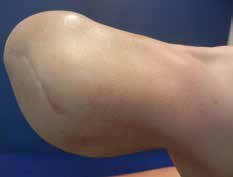

Ziel dieses Beitrages ist die Empfehlung eines Paradigmenwechsels in der postoperativen Behandlung auf der Grundlage jahrzehntelanger operativer und rehabilitativer Erfahrung in den ersten drei bis sechs Monaten nach der Amputation – wobei zu bedenken gilt, dass es eigentlich kein „echter“ Paradigmenwechsel ist, da die unten dargelegten Empfehlungen früher bereits praktiziert wurden und sich bewährt haben (Abb. 1 u. 2).

- Bei jeder Amputation handelt es sich um ein plastisches Verfahren mit großer Wund- und Narbenfläche und nicht um das bloße Abschneiden eines Extremitätenteiles. Die in der Spezialambulanz für Amputierte des Verfassers begutachteten Ergebnisse lassen aber vermuten, dass dies noch nicht allen Operateuren klar geworden ist (Abb. 3a–c).